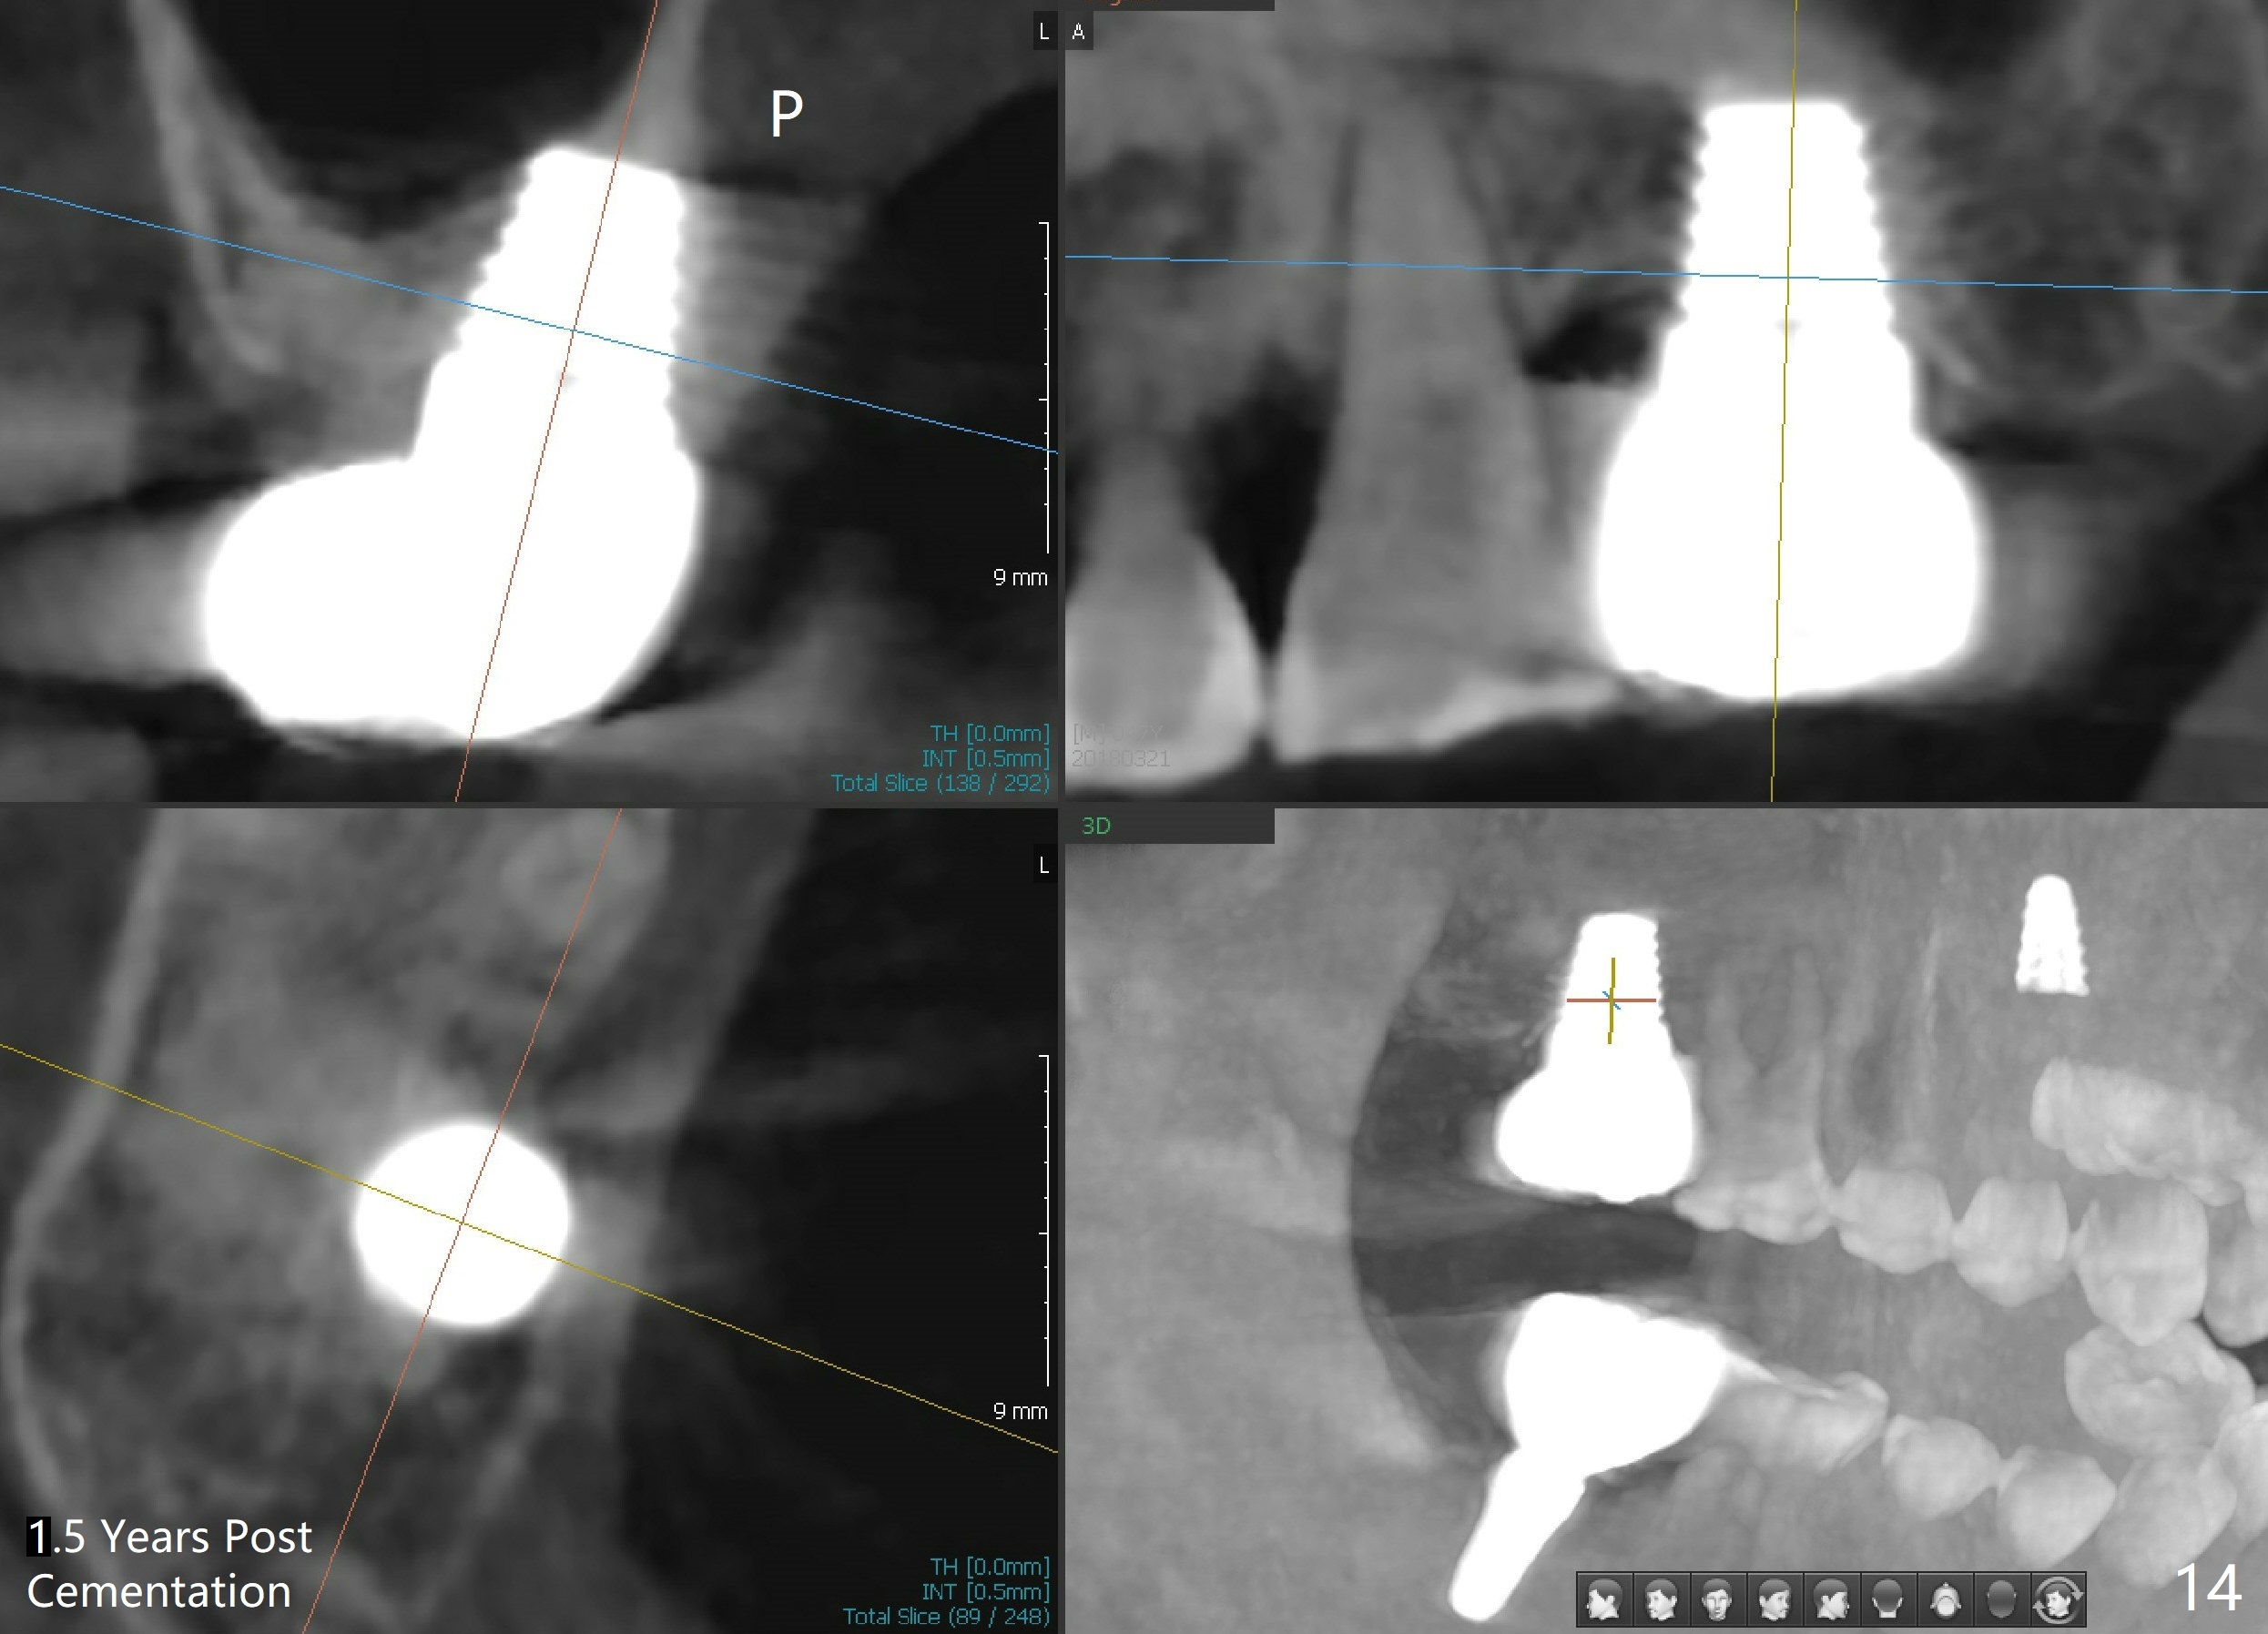

The patient returns for final restoration 22 months postop (Fig.12). Implant threads are embedded in the bone. Panoramic X-ray is taken after removal of perforated provisional and abutment. The implant remains asymptomatic 1 year post cementation (Fig.13) in spite of the fact that there appears to be no palatal plate (Fig.14 (1.5 years post cementation)). It is probably related to the thick palatal (P) gingiva. Periimplantitis develops 3 years post cementation and immediately post #15 implant 2nd removal. The implant is found to be palatal when #3 DO composite is placed (Fig.15). Oral hygiene appears to be difficult to maintain in spite of use of water pik. His diabetes is under control with Insulin.